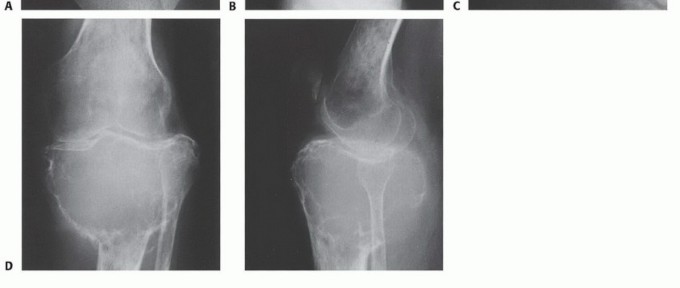

Enneking Staging System for Benign Bone Tumors

Enneking also established a robust staging system for benign osseous lesions based on clinical presentation and radiographic behavior:

* Stage 1 (Latent): Asymptomatic, discovered incidentally. Static growth or spontaneous healing. Thick, well-defined reactive sclerotic rim. Treated with observation or simple curettage (e.g., Non-ossifying fibroma).

* Stage 2 (Active): Progressive growth, mild symptoms, but contained within natural cortical barriers. Treated with extended curettage and burr drilling (e.g., Aneurysmal bone cyst).

* Stage 3 (Aggressive): Rapid growth, symptomatic, destroys cortical bone, and extends into soft tissue. Minimal to no reactive bone rim. Requires aggressive extended curettage with local adjuvants (liquid nitrogen, phenol, argon beam) or wide en bloc resection (e.g., Giant cell tumor of bone).

Imaging Set 2: Advanced Diagnostic Modalities